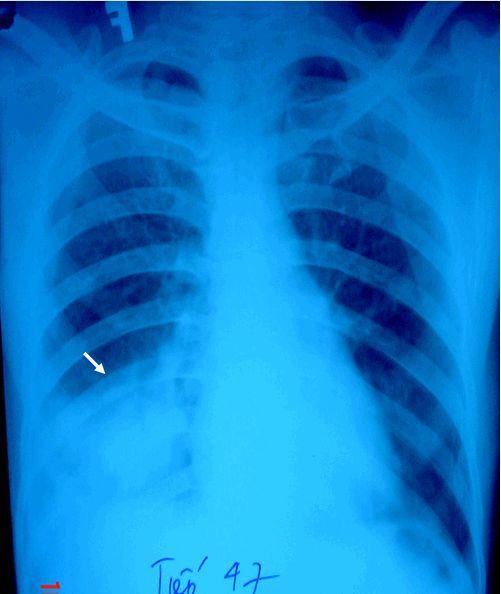

Ung thư phổi phải áp xe hoá

Ung thư phổi phải áp xe hoá trên phim chụp x quang và cắt lớp vi tính. Chẩn đoán ung thư phổi và phân loại hiện nay chủ yếu dựa trên kính hiển vi, thỉnh thoảng bổ sung bằng các xét nghiệm miễn dịch. Để biết rõ hơn về bệnh lý này mời các bạn cùng tham khảo bài viết ngay dưới đây nhé!